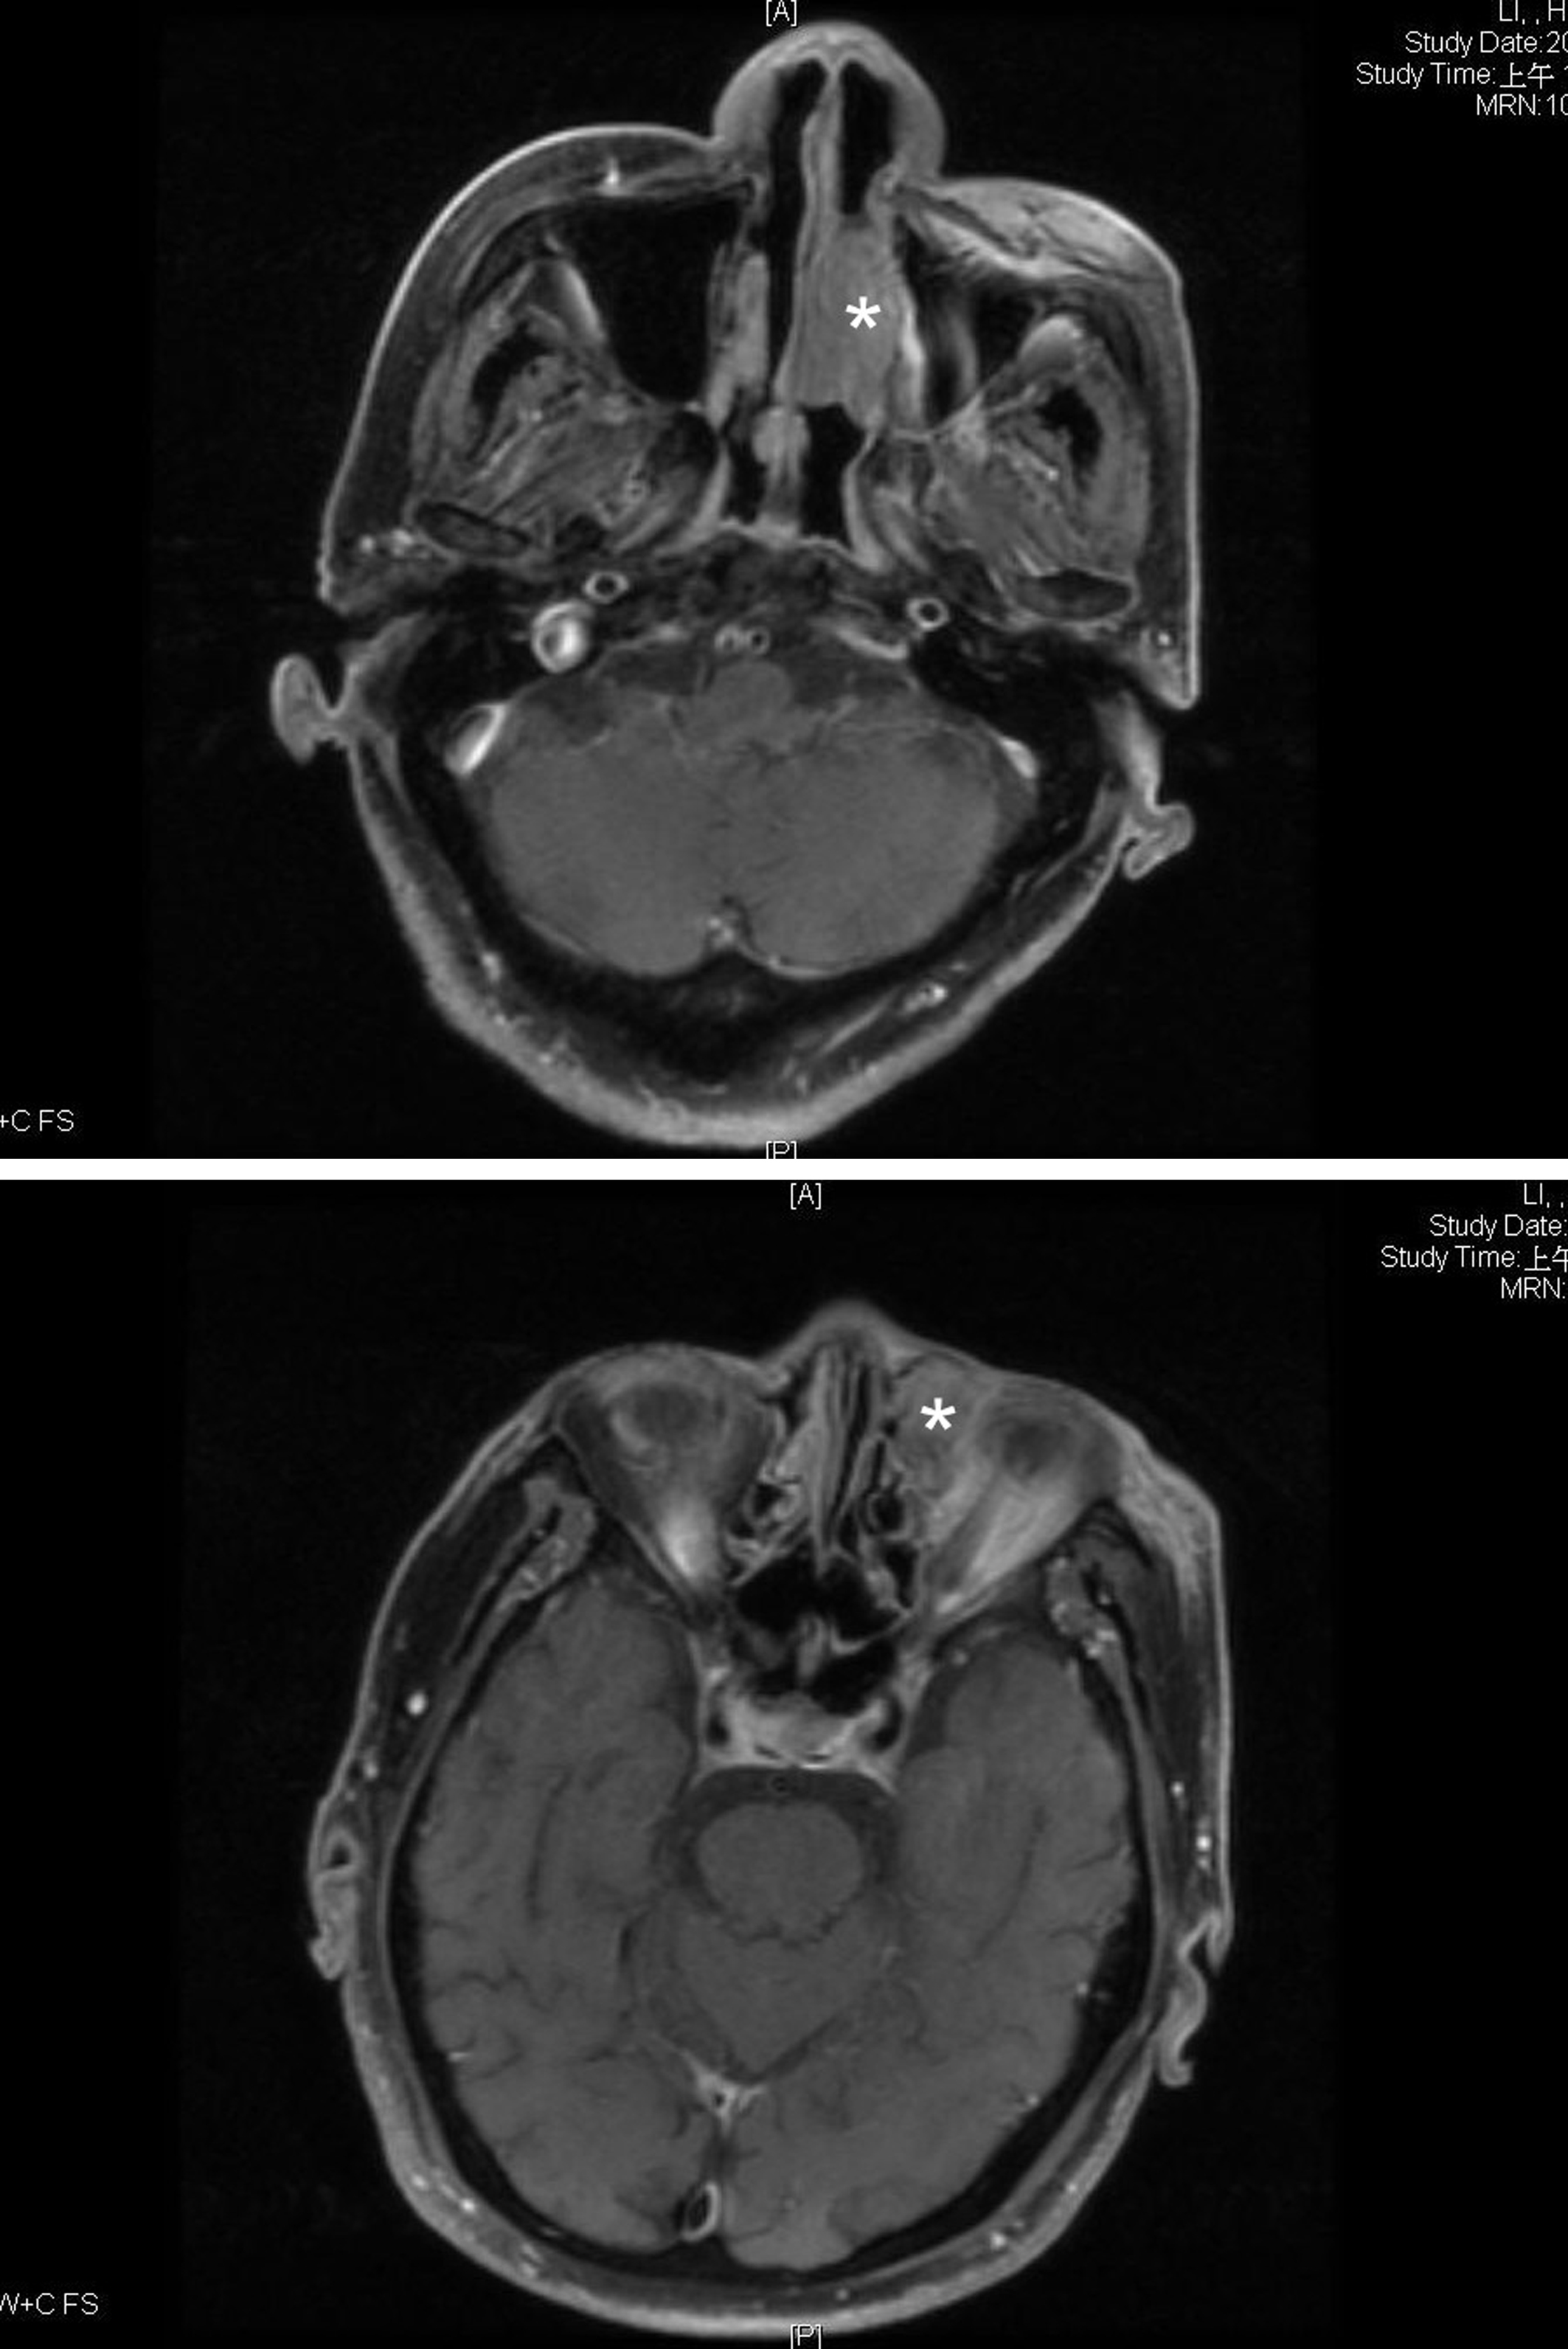

We here present a 78 year-old man with old stroke and under aspirin treatment presented with a 2-month history of nasal obstruction and epistaxis. He also developed epiphora and ocular swelling in recent 1 week in his left eye. Physical examination revealed left periorbital swelling, chemosis, lateral gaze impairment and a dark-colored mass in left nasal cavity. NLD obstruction was demonstrated by probing and irrigation. The nasal tumor was biopsied. Mucosal melanoma was diagnosed by identification of melanin in the tumor cells and positive staining with S-100. Contrast enhanced T1-weighted MRI demonstrated an enlarged hyperdense lesion in left nasal cavity (Fig. 1A, asterisk) and a hyperdense lesion in left medial aspect of orbit with involvement of preseptal space and retrobulbar fat (Fig. 1B, asterisk). Contrast-enhanced CT demonstrated a dumbbell-shaped tumor in left medial canthal region and nasal cavity, connected by the NLD (Fig. 2, arrowheads).

![]() Click for large image | Figure 1. Contrast enhanced T1-weighted MRI showed (A) an enlarged hyperdense lesion in left nasal cavity (asterisk), (B) A hyperdense lesion in left medial aspect of orbit with involvement of preseptal space and retrobulbar fat were found on (asterisk). |